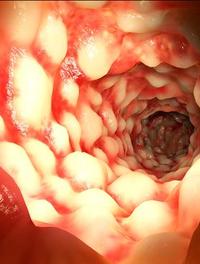

Le syndrome du côlon irritable avec diarrhée (SII-D) est une affection fréquente et parfois difficile à traiter qui réduit significativement [...]

Bien que l’on ne connaisse pas avec certitude les causes du syndrome de l’intestin irritable (SII), il est probable que ce trouble [...]

Le syndrome du côlon irritable à prédominance diarrhéïque (SII-D) est l’un des diagnostics les plus couramment posés par les gastro-entérologues. [...]

Le syndrome du côlon irritable (SCI), qui touche 20 % de la population occidentale selon l’Agence européenne de médicine (EMA), est [...]

La colonoscopie est aujourd’hui la technique de référence pour explorer le côlon et le rectum et tout particulièrement pour dépister [...]